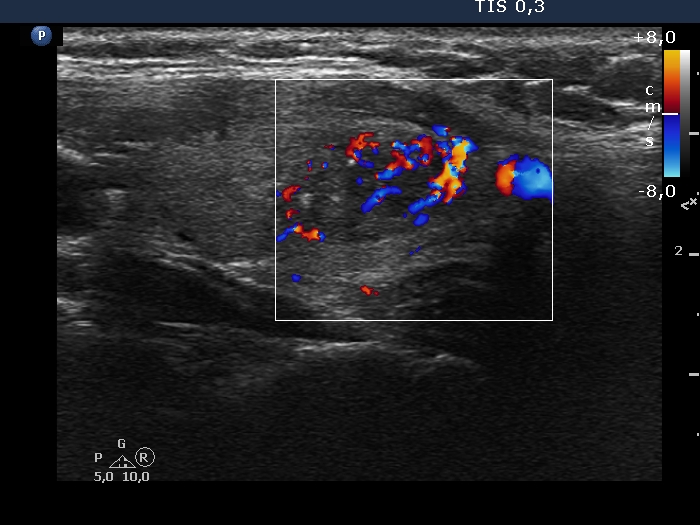

100 consecutive cases of papillary cancer - case 089 (ultrasonographic picture 7)

Right lobe, longitudinal scan

Left lobe longitudinal scan, color Doppler mode. The lesion has intranodular vascularity, too.